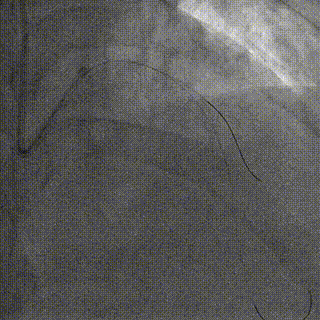

PCI过程

7F XB3.5,Cosair,Runthrough中间支保护,Pilot200正向进入D1,Pilot200 无法通过病变,交换Judo导丝

更换Judo3顺利到达LAD远端,Cosair跟进交换Runthrough

Ballon 2.0*15mm Dilatation & IVUS check

LAD-LM DES 2.75*20mm,2.75*18mm,3.0*30mm

Ballon 2.0*15mm Dilatation for D1 Ostial

NC Ballon & IVUS check

Final result:TIMI3